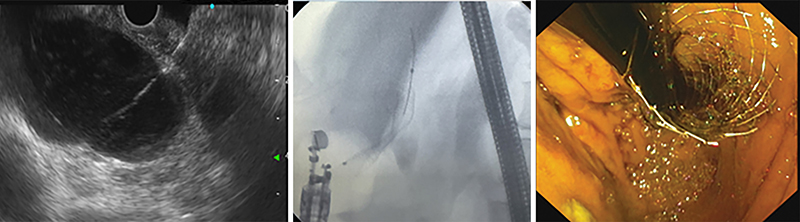

EUS-HGS (EUH-vezérelt hepaticogastrostomia)

Az eljárás során a gyomor felől a máj bal lebenyének S2 (könnyebb manipuláció, de súlyosabb szövődmények) vagy S3 epeútjait (nehezebb manipuláció, de biztonságosabb) (14) drenáljuk speciális öntáguló fémstenttel (SEMS) (2. ábra), vagy ritkábban plasztikstenttel (3. ábra), amelynek a májban levő része fedetlen, míg a máj és a gyomor között fedett. Az eljárás során a kiválasztott epeutat egy 19G-s EUS-tűvel pungáljuk, majd epeaspirációt végzünk, az eperendszer kontrasztos feltöltése során 0,035-es vagy 0,025-es vezetődrótot helyezünk be. Ezután fistulaképzést végzünk (6 Fr cystotom ± ballon), és végül a speciális fémstenttel kialakítjuk a drenázst (15). Az eljárás technikai sikeraránya 96,6–97,7%, míg a klinikai sikeressége 88,1–91,1%, de a nemkívánatos események aránya magasabb (12–17,5%), mint az EUS-CDS-nél tapasztalt 12,2% (16, 17). Ezen sikerességi arány eléréséhez hosszú tanulási görbe vezet (>4 év) (17). Az ESGE ajánlása szerint EUS-HGS csak inoperábilis malignus hilaris epeúti szűkületben javasolt tág bal eperendszer esetén, nagy volumenű centrumokban (18).

18 cm hosszú, 7 Fr-es double pigtaillel. Roux-Y-műtét után kialakult benignus distalis epeúti elzáródás kezelésére (1)